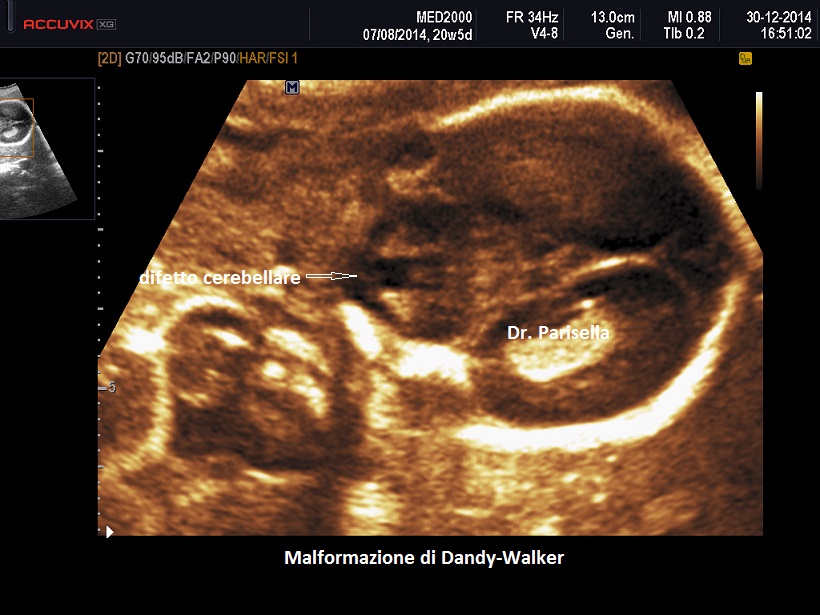

Sindrome o Malformazione di Dandy-Walker

La malformazione di Dandy-Walker ha una incidenza di circa 1/30.000 nati ed è caratterizzata da agenesia totale o parziale del verme cerebellare e dilatazione cistica del 4° ventricolo; se il verme è ipoplasico esso appare dislocato anteriormente e superiormente.

La diagnosi ecografica si basa su:

• dilatazione cistica del IV ventricolo che si estende occupando gran parte della fossa cranica posteriore; la cisterna magna è compressa tra il 4° ventricolo dilatato e la dura madre

• ipogenesia o agenesia del verme cerebellare

• ampia separazione degli emisferi cerebellari: caratteristica è la schisi a "V" del verme cerebellare nel piano assiale

• sul piano mediano il 4° ventricolo dilatato si estende superiormente dislocando il verme cerebellare, che è frequentemente ipoplasico